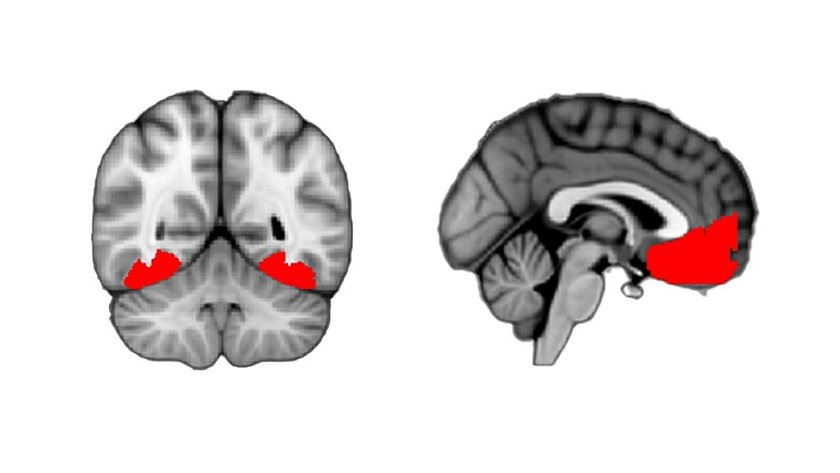

Области, которые активны при любопытстве

Также ученые выяснили, что при высокой степени заинтересованности задействуется затылочно-височная кора. Это область возле ушей, которая участвует в регулировании зрительных функций, а также в распознавании объектов.

Помимо этого, активность зафиксировали в двух областях в передней части мозга — передней поясной извилине и вентромедиальной префронтальной коре. Такие зоны отвечают за сбор информации и определение ценности.